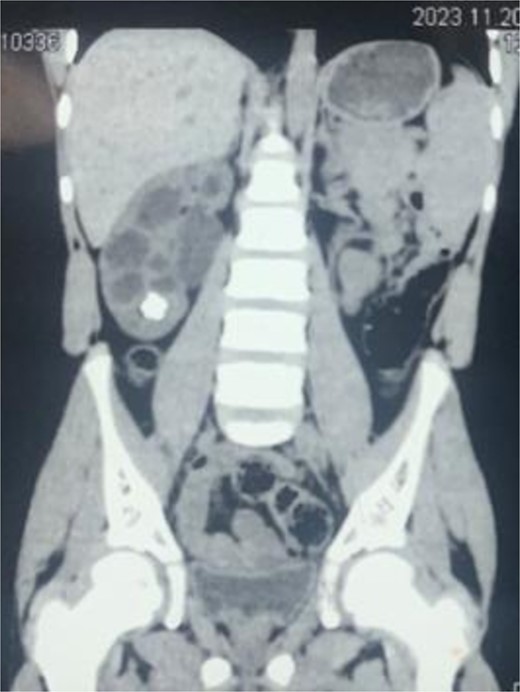

A 16-year-old male presented into hospital with mainly a complaint of right-sided flank pain that was mild to moderate in intensity, radiating toward the back for a month. The pain was associated with dysuria, urinary urgency and frequency, and occasional hematuria. There was no previous surgical or medical history with insignificant findings on physical examination. His creatinine was 0.5 mg/dl. On ultrasound, there was right renal lithiasis with moderate hydronephrosis, minimal hydroureter, cortical thinning, and pyonephrosis. CT scan demonstrated 12.9 mm calculus in the lower calyx (Fig. 1). Moderate hydronephrosis was visualized with markedly dilated renal pelvis with abrupt narrowing, measuring 38 mm in diameter. On the DTPA renal scan, the glomerular filtration rate (GFR) was 21.9 ml/min (Fig. 2). It showed an obstructive curve which helped in the definitive diagnosis of PUJ obstruction for which LP was planned.